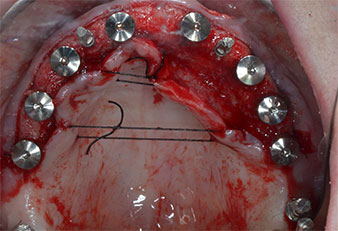

Три години по-късно е дошло времето за максиларна протеза от същия тип. Въз основа на планирането със CBCT, аугментацията на синусите е избегната с помощта на къси импланти и използването на хирургичен шаблон, за да се прехвърлят планираните позиции в алвеоларния гребен. (Фиг. 1 и 2).

Фиг. 1 Предварителен изглед на максиларния гребен с позиции на имплантите, маркирани с помощта на хирургичен водач. Поради ниския алвеоларен гребен са планирани супер къси импланти в дисталните зони.

Позиции на имплантите

Фиг. 2 След инцизия в средата на алвеоларния гребен и препариране на мукопериостални ламба, позициите на имплантите са трансферирани в костта.